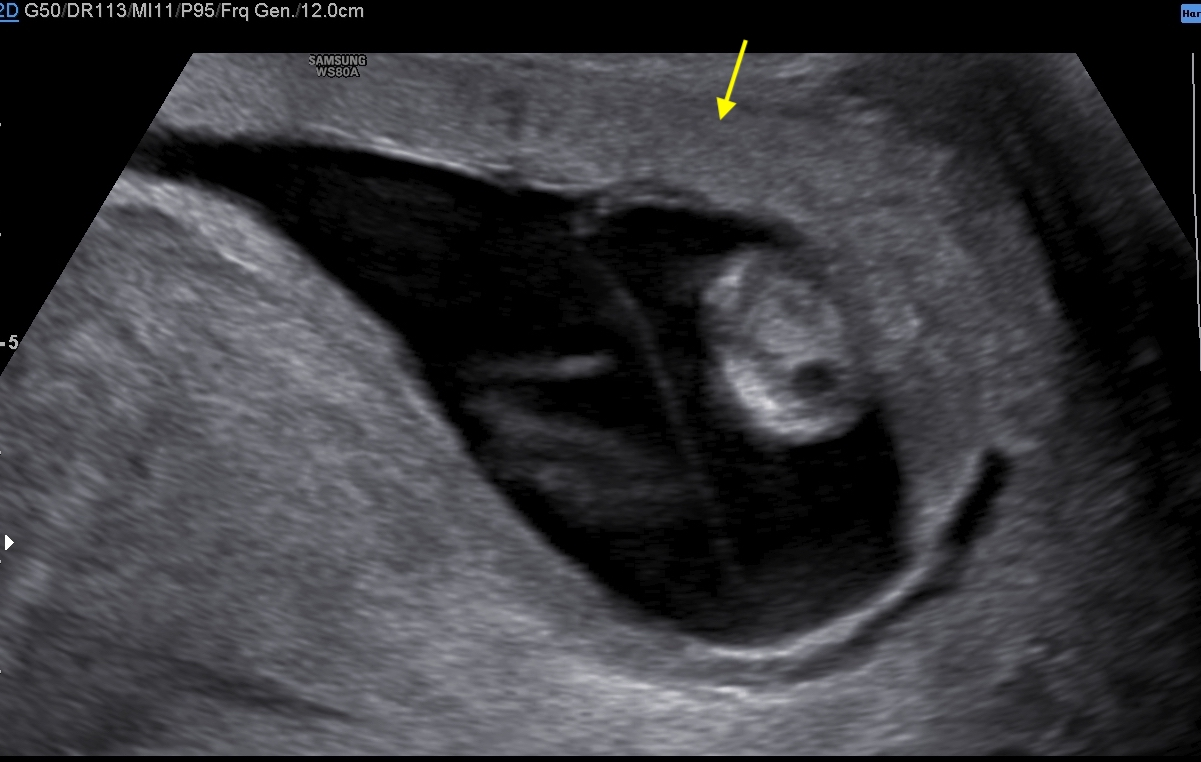

A healthy 39-year-old woman G4P3 was admitted to our high-risk pregnancy outpatient service due to a MC-DA twin pregnancy. Monochorionicity was suspected by the referring gynecologist during the dating ultrasound scan (US). The nuchal translucency US at the 12th week of gestation highlighted a “T” sign of the dividing membrane with a unique anterior placenta confirming a MC-DA twin pregnancy, as shown in Fig. 1. Soft markers for trisomy were found to be normal for both twins. The US performed during the 14th week of gestation showed the twins significantly closer to each-other standing on the same side of a free-floating thin membrane inserted on the placenta. This image raised the suspicion for a spontaneous septostomy (Fig. 2). The patient underwent amniocentesis as the combined serum screen showed an increased risk for Trisomy 21. US assisted invasive procedure did not detect the dividing membrane deposing for a PMM twin pregnancy following SS. A single sample of amniotic fluid was obtained and tested normal for fetal karyotype (46, XX). According to International Guidelines US imaging was performed every two weeks. Anomaly scan was normal and all subsequent Doppler US showed a normal twin growth and fetal wellbeing until the early third trimester [14, 15, 16]. The US performed at the 27th week of gestation showed a strict contiguity of the umbilical cords with a suspicion for cord entanglement on 3-dimensional (3D) US (Fig. 3A,B). The patient was hospitalized for close pregnancy surveillance. Fetal heart monitoring and US scan were daily performed. Steroids were administered for prevention of respiratory distress syndrome. The 29th week US scan highlighted a growth discordance ranging around 21% (symmetric growth at the 71° centile (estimated weight: 1328 gr) and at the 36° centile (estimated weight: 1043 gr) for Twin A and Twin B respectively). An episode of prolonged bradycardia was registered for Twin A. An emergency cesarean section was performed: two healthy girls were born (Twin A: weight 1360 gr, Apgar 4 and 7 at 1st and 5th minute respectively — Twin B: weight 1000 gr, Apgar 8 and 9 at 1st and 5th minute respectively). Cord entanglement was confirmed as shown in Fig. 4. The mother’s postoperative recovery was uneventful. Twins’ developmental follow-up at 12 months of age was normal.

Fig. 1.Sonogram depicting the “T” sign of the dividing membrane with a unique anterior placenta.